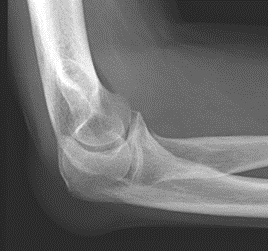

Które zdjęcie RTG stawu łokciowego zostało wykonane w projekcji skośnej w rotacji zewnętrznej?

A. Zdjęcie 1

B. Zdjęcie 2

C. Zdjęcie 3

D. Zdjęcie 4